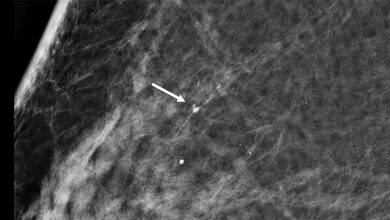

Tengteng Wang, PhD, MSPH, und Marilie Gammon, PhD, von der University of North Carolina at Chapel Hill, fragten sich, ob die DNA-Methylierung die Wirkung von Aspirin bei Patientinnen mit Brustkrebs beeinflussen kann. Das Team untersuchte die DNA-Methylierung im Brusttumorgewebe und auch in Zellen, die im Blut von Patienten zirkulieren. Die Studie ist laut der Studienautoren die erste, die den Effekt der DNA-Methylierung auf den Zusammenhang zwischen Aspiringebrauch und Mortalität bei Frauen mit Brustkrebs untersucht hat.

In der Studie wurden 1.266 Frauen, bei denen im Zeitraum 1996-1997 Brustkrebs diagnostiziert wurde, erfasst. 476 davon starben später an einer anderen Ursache und 202 Teilnehmerinnen starben bis Ende 2014 an Brustkrebs. Bei denjenigen Frauen, die Aspirin verwendeten, war das Risiko, an einer anderen Ursache zu sterben und das Risiko, an Brustkrebs zu sterben, geringer, wenn deren DNA im Gebiet, das die Expression des brustkrebsbezogenen BRCA1-Gens kontrolliert, nicht methyliert war. Andere Methylierungsmuster im Zusammenhang mit Aspiringebrauch und Mortalität wurden ebenfalls beobachtet.